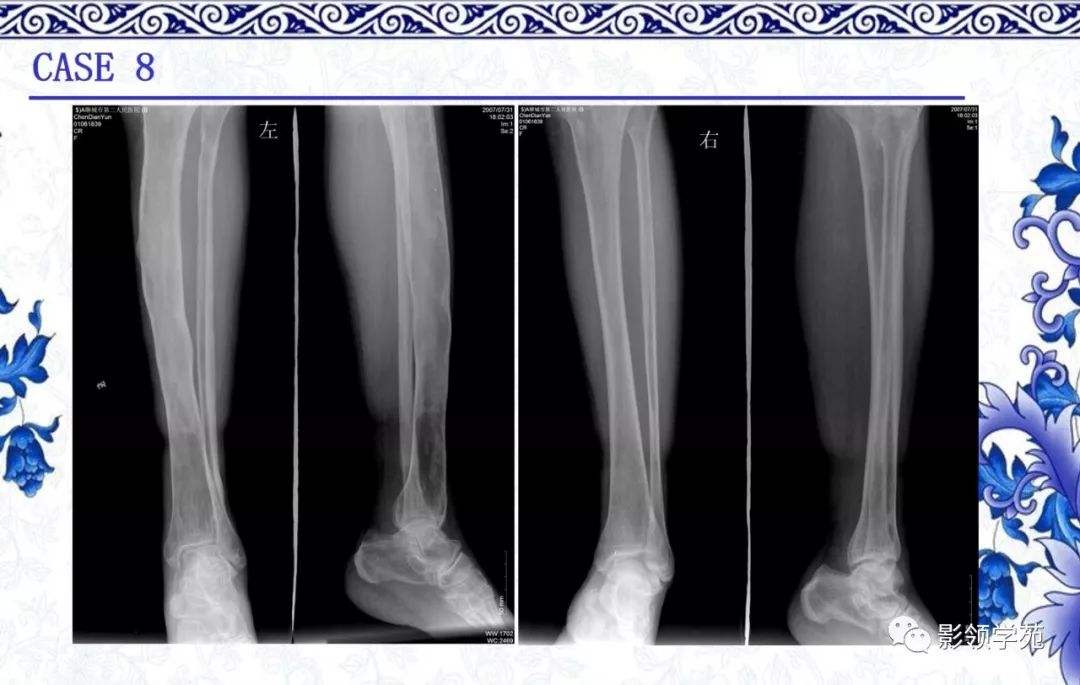

骨纤维结构不良是一种骨骼系统的慢性疾病,具体表现为骨纤维组织的异常增生从医学角度来看,它属于良性肿瘤的一种,多数情况下是由于先天性发育问题或内分泌系统的失调所引发的值得注意的是,并非所有患有此病的患者都会表现出明显的症状,因此,在没有明显不适的情况下,患者可以选择暂时不进行治疗;骨纤维结构不良的具体原因至今不明虽然有观点认为它与遗传有关,但至今缺乏确凿的证据这种疾病主要在大腿股骨中下段出现,四肢和面部也是较为常见的部位尽管有遗传因素的假设,但实际发病机制仍有待进一步研究骨纤维结构不良是一种骨骼发育异常的疾病,其具体病因尚未完全明确尽管有人认为它与遗传;骨纤维结构不良是一种骨骼的良性病变以下是关于骨纤维结构不良的详细解答1 病因 目前骨纤维结构不良的具体原因尚不清楚,可能与先天发育异常成骨障碍或内分泌异常有关2 症状 骨纤维结构不良可能没有明显的症状 部分患者可能出现局部疼痛 有时在发生病理性骨折后,通过拍片检查才发现该;骨纤维结构不良是先天性非遗传性以骨纤维异常增生为特征的类肿瘤疾患,可分为单骨型单处发病多骨型全身多处骨骼有病灶及多骨伴皮肤色素沉着内分泌障碍的McCuneAlbright综合征MAS单骨型多在10岁左右发病,四肢病损常位于近侧端,长骨病损常位于干骺端,可局限或向骨干扩散临;骨髓纤维异常增殖症现称为骨纤维发育不良,又称骨纤维结构不良,是一种良性病变以下是关于该病的详细介绍好发于特定人群此病临床多见,好发于青少年和中年人,尤其高发于骨骼生长旺盛阶段的1025岁人群病变特征病变的骨骼可以是单一部位,也可以是多处骨骼其特征是在骨髓腔内有纤维化骨骼形成;骨纤维结构不良是发生于形成骨的间充质的发育畸形,属于骨内纤维组织增生的病变,临床表现多以长骨病变为主,大多数病变是孤立的单骨病变,多数人的主要症状是轻微的患肢疼痛,肿胀以及局部压痛,部分人当出现病理骨折时才发现该病患侧肢体可出现弯曲畸形,X线表现主要为长股骨长管状骨的干骺端或骨干有。

骨纤维结构不良疾病的病理主要表现为以下几个方面病变组织异常增生主要包括纤维组织和新生的骨小梁纤维组织由细长的梭形细胞构成,结构不规则,质地和颜色多样大体检查特征病变通常呈现膨胀性,被完整包膜包裹内部结构各异,包括灰白色质地坚韧的区域,以及可能含有透明软骨的囊性变区域显微镜;骨纤维结构不良是一种良性骨病变临床表现患肢可有肿胀,疼痛局部皮肤可有咖啡斑易发生病理骨折指导意见病变到 青春期 多停止发展,因此治疗宜保守观察,如有病理骨折或有进行性骨畸形可手术,刮除植骨,建议结合临床考虑,谢谢。

回答病情分析 你好骨纤维结构不良又称骨纤维异常增殖症,系正常骨组织逐渐被增生的纤维组织所代替的一种较常见的良性病变,属于骨软骨发育异常是骨的纤维组织发育紊乱,异常增生所致本病可侵犯单骨或多骨,合并皮肤色素沉着和性早熟等内分泌紊乱,则称为奥氏综合症本病多发生于儿童,由于进展缓慢又无;这种疾病也称作骨纤维异样增殖主要是在纤维组织增生的时候,有骨小梁生成纤维组织增生并且成骨,但是这个骨头是幼稚的骨头而不是人体正常的骨质所以这个骨头的质量就比较差,容易导致骨头的病损会出现局部的疼痛,畸形,骨头的质量下降,很多患者会发生病理性的骨折这种疾病首先可以进行保守治疗;骨纤维结构不良,又称之为骨纤维异常增殖症,是临床上骨肿瘤样病变发病率最高的一种疾病,也是肋骨最常见的良性病变骨纤维结构不良发病的病因并不完全明确,可以累及全身多个骨骼,常见于青少年,女性患者相对较多,全身所有骨骼几乎都可以累及,鉴别上需要与急性骨炎和内生软骨瘤相鉴别一般骨纤维结构不良。